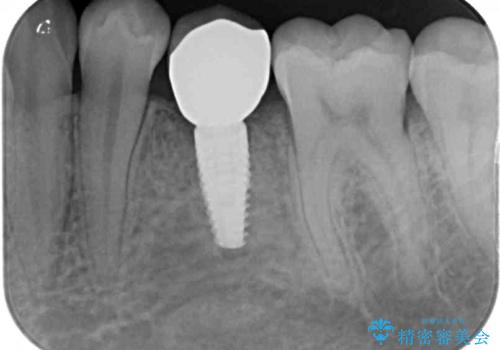

左下には後続永久歯の欠損した乳歯が残存しており、叢生を相まって咬合関係が乱れていました。

乳歯は抜歯し、インビザラインにて矯正治療を行いながら、並行してインプラントによる補綴治療を行うこととしました。

矯正治療が終わるタイミングに合わせてインプラントの埋入を行っていたので、矯正治療を終了すると同時にセラミック補綴治療を行えました。